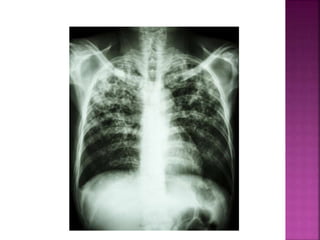

1. Pulmonary coccidioidomycosis

2. Disseminated coccidioidomycosis